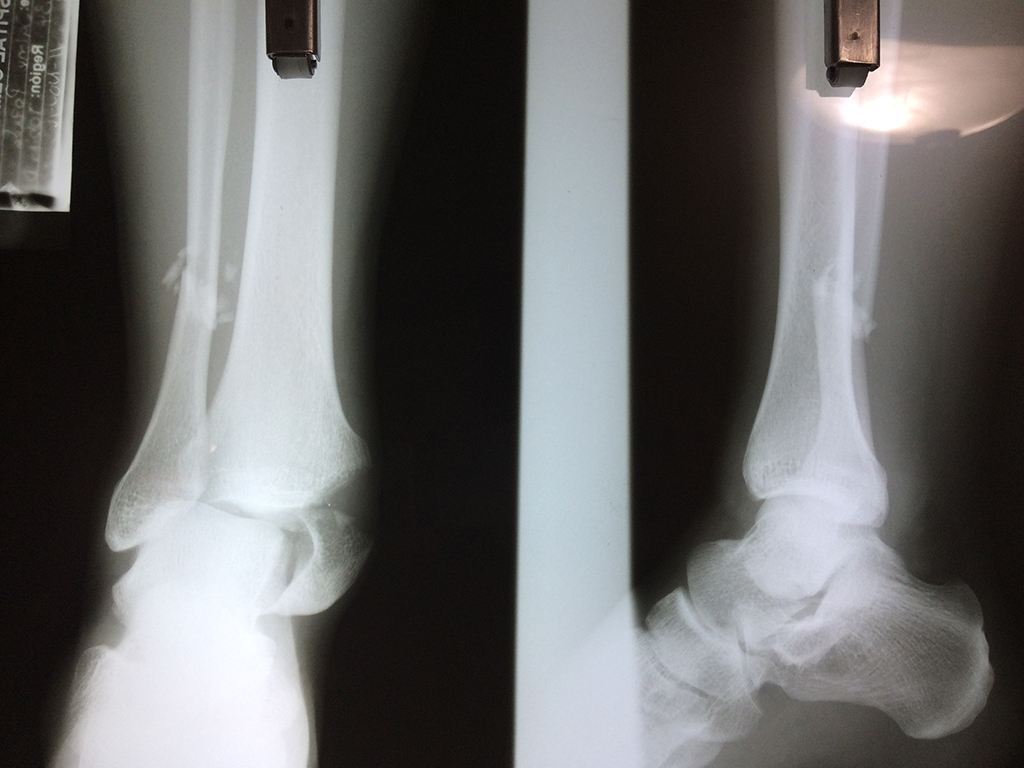

Una fractura de tobillo es la rotura de uno o más de los huesos del tobillo. Estas fracturas pueden ser:

- Parciales (el hueso está sólo parcialmente fisurado, no del todo).

- Completas (el hueso está perforado y está en 2 partes).

Cuando se necesita cirugía, es probable que esta implique el uso de clavijas de metal, tornillos o placas para sostener los huesos en su lugar mientras la fractura se consolida. Los elementos de soporte pueden ser temporales o permanentes.